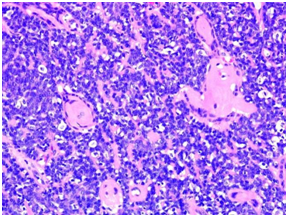

Diagnosis was a complete margin excision Eccrine Spiradenoma with an unusual cystic pattern (Figures 5)(Figure 6) having a luminal cell population, CK8/18 positive (Figure 7), and a basal and myoepithelial cells population, p63 positive (Figure 8).

Figure 6 Eccrine spiradenoma is a nodular tumor, constituted by small cells, with lymphoid infiltrate (H&Estain, ob. x20).